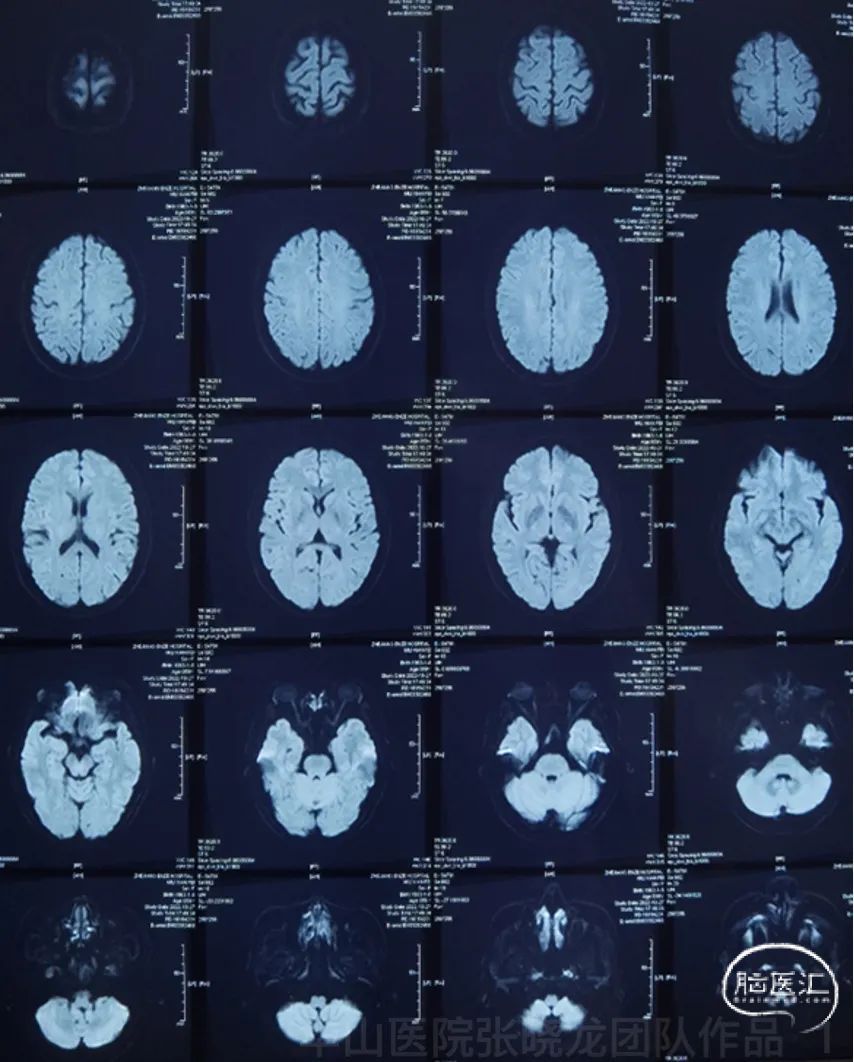

Figure 1. DWI did not reveal any acute infarctions.

图 1. DWI未见急性脑梗灶。